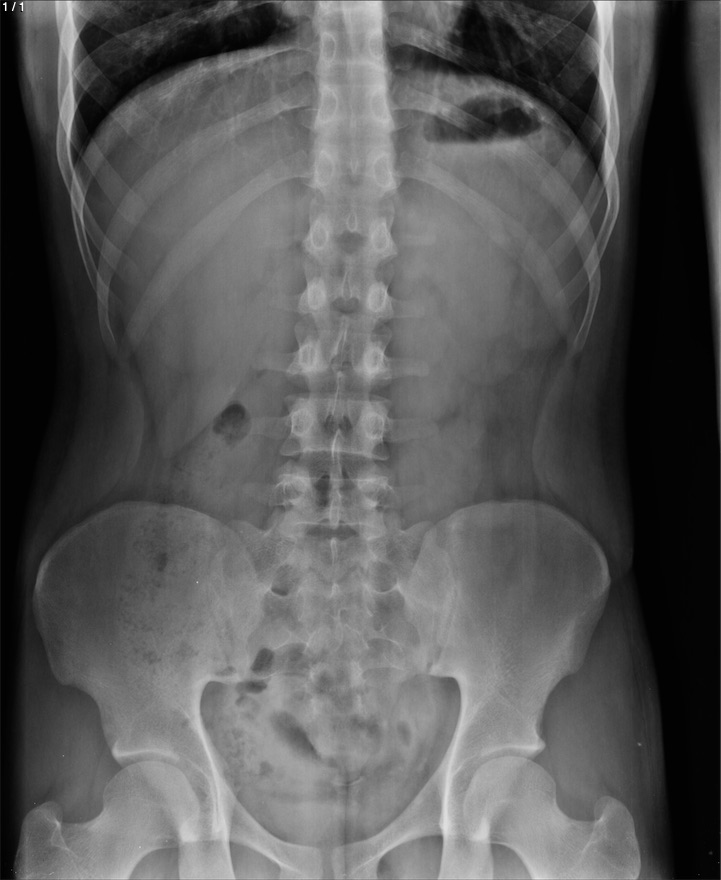

Yerit Antonio Espinoza Ponce - Unnamed